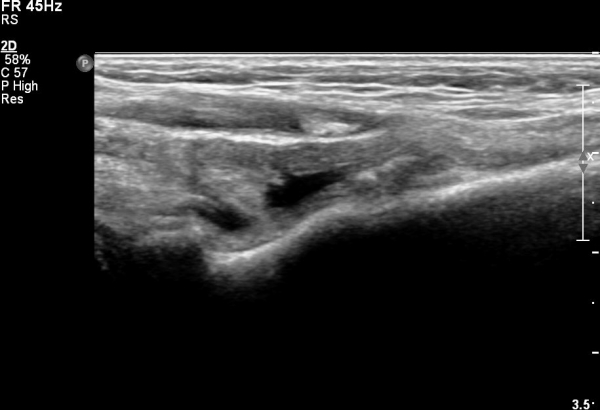

ÆÈ²ÞÄ¡ ¾Õ ÀÌµÎ¹Ú±Ù°Ç È¸´Ü¸ç°Ë»ç¿¡¼­ ÀÌµÎ¹Ú±Ù°Ç ¿ÜÃø¿¡ ¼ö¾×Àú·ù°¡ °üÂûµÊ(»çÁø 1).